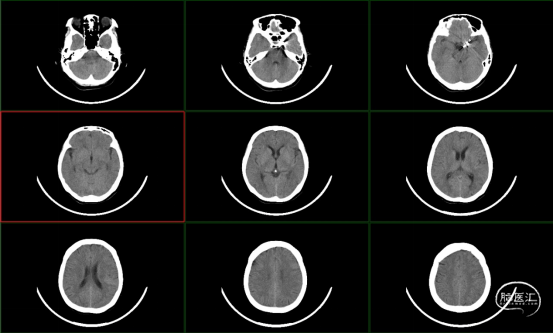

术后13天CT